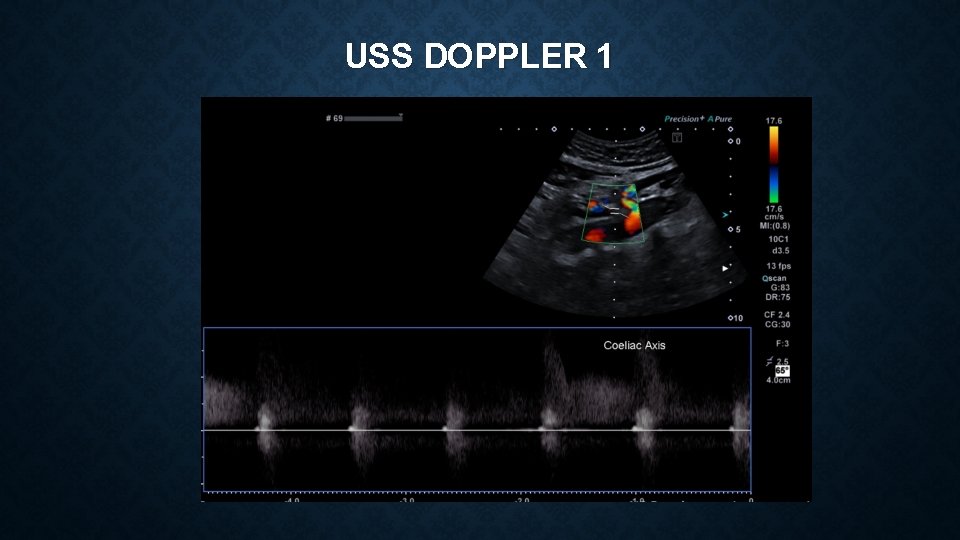

USS DOPPLER 1

MEDIAN ARCUATE LIGAMENT SYNDROME Vague constellation of symptoms which can include : • epigastric pain, postprandial pain, chronic non-specific abdominal pain, nausea, vomiting, weight loss Often a diagnosis of exclusion – reliant on clinical features and imaging findings Investigations include – CT angiogram and duplex ultrasonography CT – focal narrowing of coeliac artery with post-stenotic dilatation USS – Peak systolic velocities of >200 cm/s are suggestive of MALS